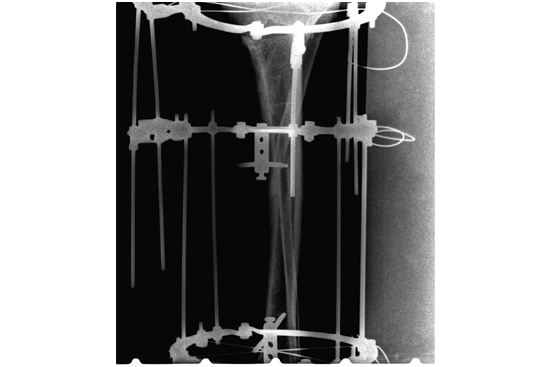

HTO Ilizarov